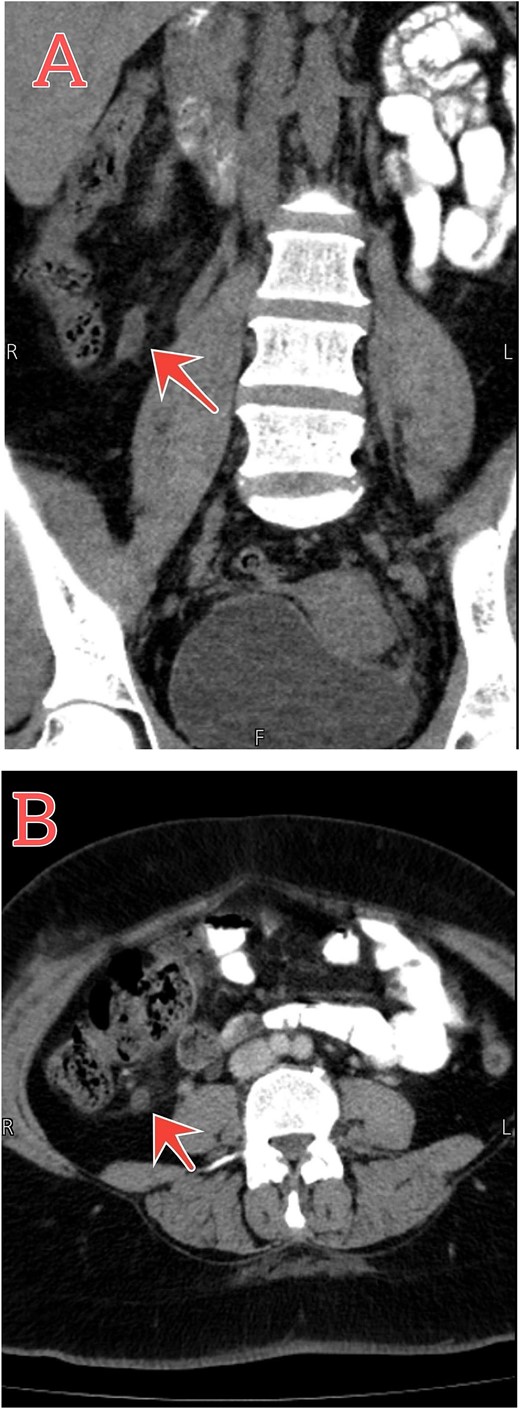

Further investigations were done to confirm the diagnosis, CBC showed elevated WBC with left shifting, and C-reactive protein (CRP) was positive at 16 g/l. gynecological consulted to exclude any gynecological cause, the ultrasound was free. Urine analysis was done, and it was free. For that, with the history of initial appendectomy, subsequent abdomen, and pelvic computed tomography (CT) with contrast was performed. Findings represent inflammation of the distal part of the residual appendix associated with mucosal enhancement and mild surrounding fat stranding, confirming the diagnosis of recurrent tip appendicitis (Fig. 1).

Abdomen–pelvic CT scan shows tip appendicitis. (A and B) Coronal and axial sections show the distal part of a blind-ended tubular structure measuring about 8 mm arising from the cecum (red arrows), associated with mucosal enhancement and mild surrounding fat stranding.